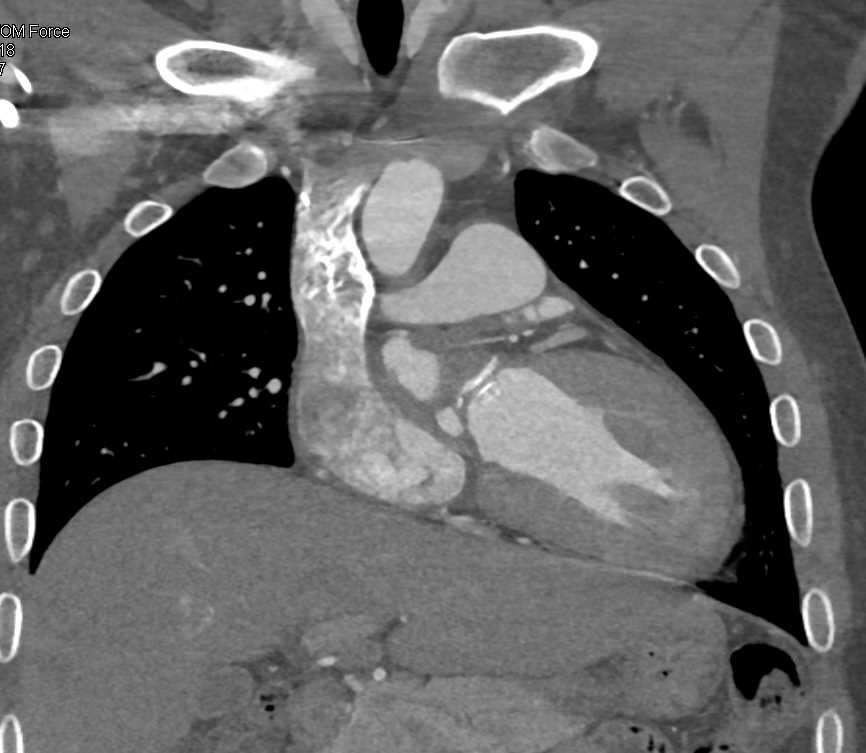

Aortic Valve Repair